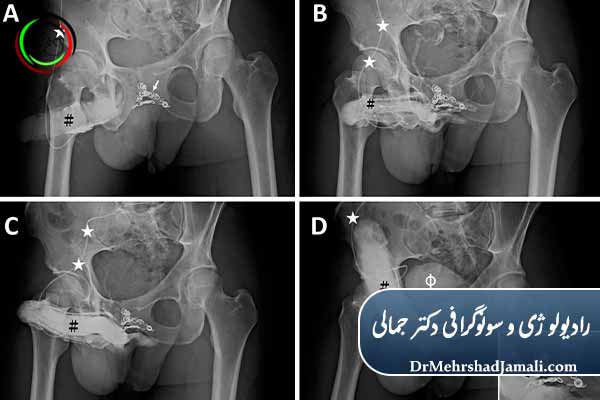

مراحل انجام آمبولیزاسیون پنیس چگونه است؟

بررسی و تشخیص دقیق

بررسی جریان خون آلت تناسلی

انجام آمبولیزاسیون

ورود از طریق یک رگ کوچک (معمولاً کشاله ران یا بازو)

بدون برش جراحی

بدون بیهوشی عمومی

با هدایت تصویربرداری پیشرفته